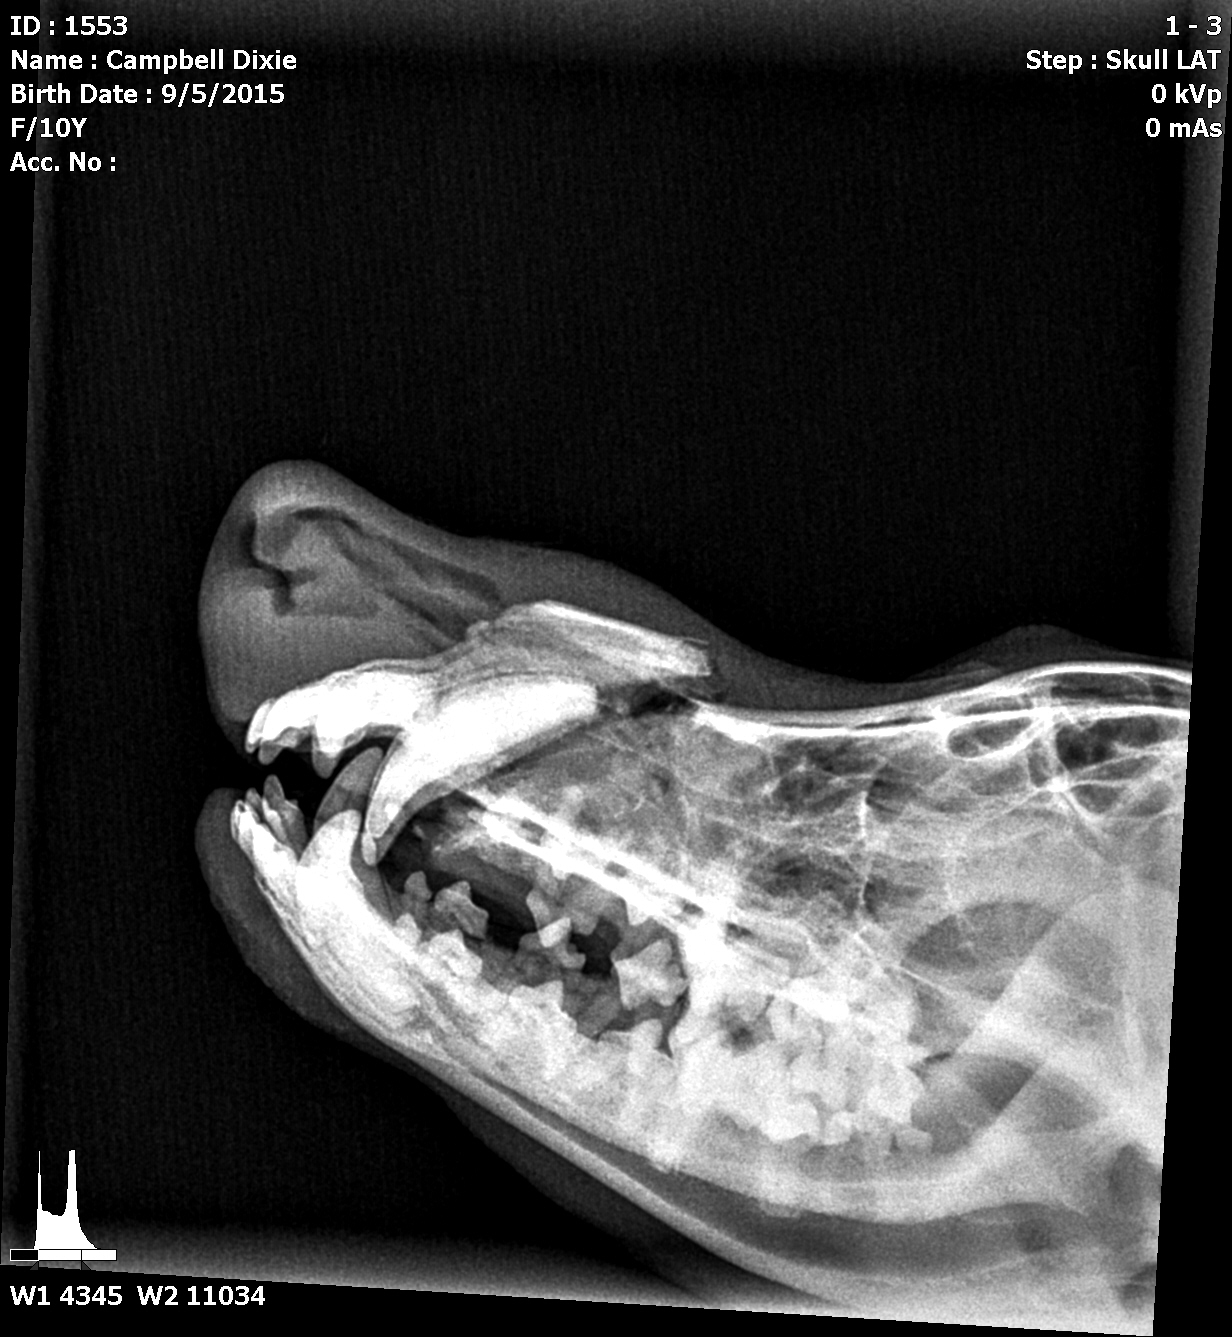

Dixie is out sugery..5.5 hours she is doing well.. best dog ever Dixie is my 10.5-year-old cream girl and my absolute favorite dog. She’s been by my side through so much, and it breaks my heart to see her in pain. Recently, Dixie had a terrible accident and broke her nose completely behind her canines. The injury is severe—she needs a plate, a partial root canal on her canines, and an intraoral splint to keep the roof of her mouth aligned. Right now, she can’t eat or drink, and she struggles to breathe through her nose.